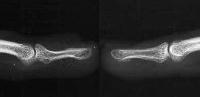

Plain films confirmed a concave contour deformity of the dorsal aspect of the distal phalanx, shown here compared to the opposite, normal finger film: